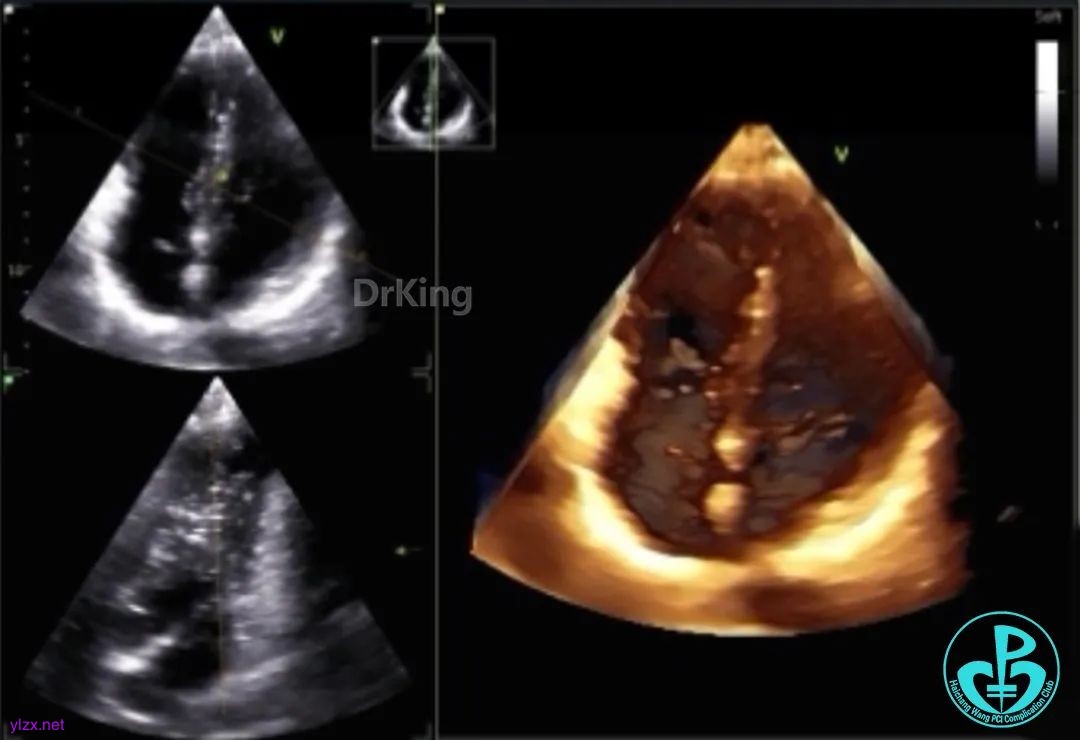

主动脉短轴切面下观察,封堵器位置正确呈Y字形抱住主动脉根部,形态良好,未见残余分流。

剑下双房心切面显示封堵器呈夹持稳定。

完全释放后超声观察封堵器形态良好,未见分流,封堵成功。